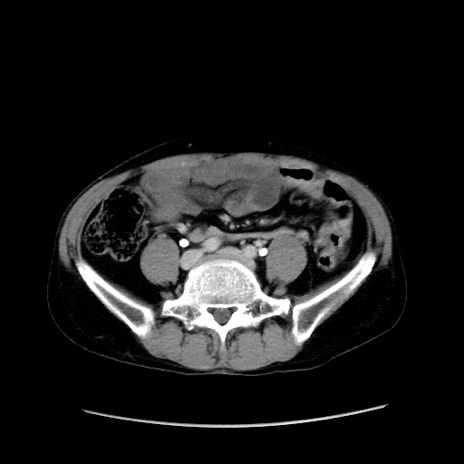

症例37(横断像)

【症例】40歳代 男性

【主訴】腹痛

【現病歴】4時間ほど前に電車に乗車中に臍部上より腹痛出現。徐々に増悪し起立困難となり、救急外来受診。生ものは数日食べていない。今朝お雑煮を食べた。

【身体所見】BT 36.8℃、BP 117/84mmHg、HR 91/min、SpO2 97%、苦悶様、腹部:臍上部広範囲圧痛あり、反跳痛±

【データ】WBC 8100、CRP 0.03